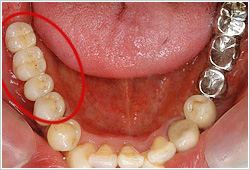

【治療前】

結合組織移植術(下がってしまった歯茎の見た目を改善したい)

【治療前】

歯茎が下がって、歯の根っこが見えています